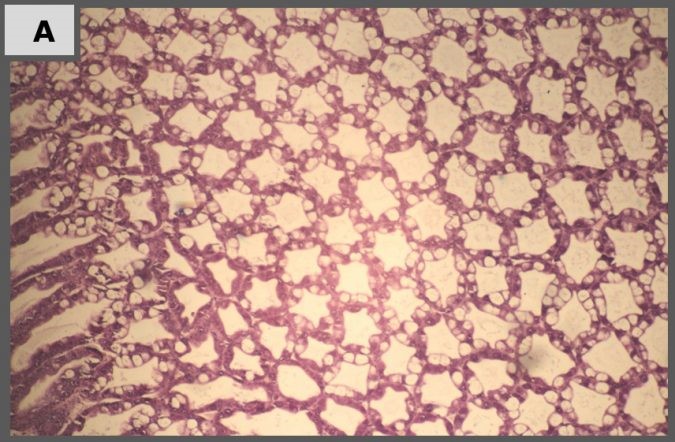

Hình 4A: Đối chứng âm: mô học gan tụy bình thường, với các loại tế bào biệt hóa, đáng chú ý là tế bào B có không bào.